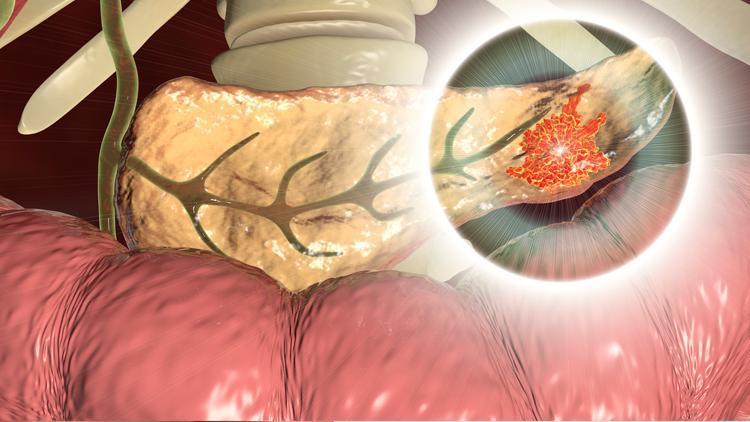

Pankreas kanseri hem sinsi hem hızlı ilerliyor!

Sindirim sisteminin bir parçası olan pankreas, karnın üst kısmında mide ve karaciğerin arkasında yer alıyor. Sindirim enzimleri ve kan şekerinin düzenlenmesini sağlayan insülin hormonunu üretiyor. Pankreası oluşturan hücrelerin aşırı çoğalmasına bağlı olarak gelişen pankreas kanseri erken evrelerde ne yazık ki belirti vermiyor. Bu nedenle pankreas tanısının zor ve geç konabildiğini belirten Dr. Türker Egesel, hastalığın ilerlemesine bağlı olarak ortaya çıkan belirtiler hakkında şunları söylüyor: